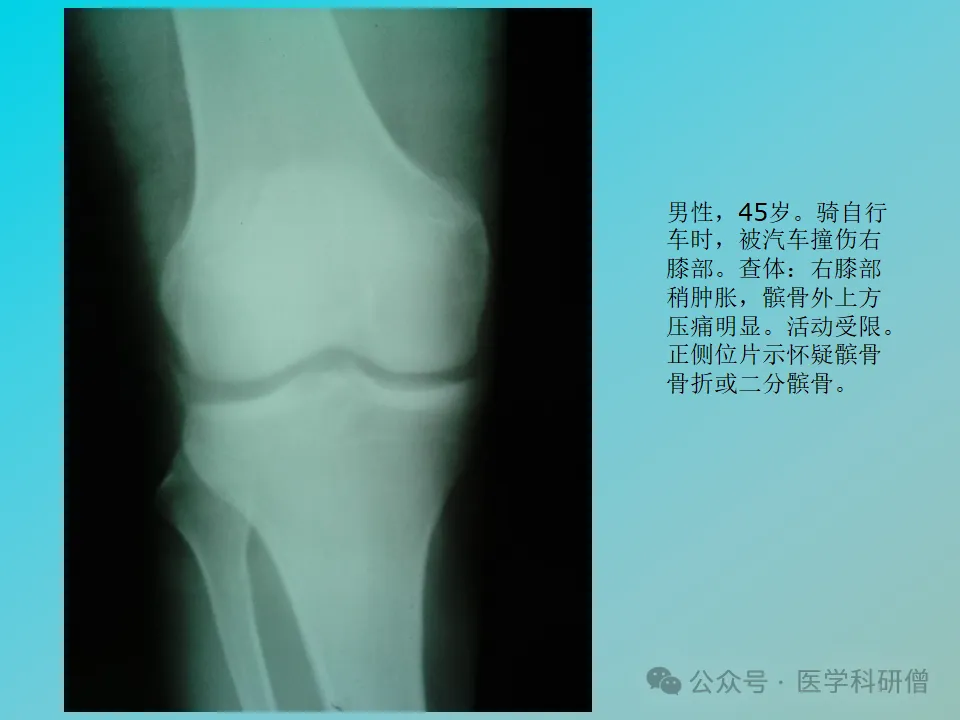

虽然文档中没有详细说明骨折的分类,但值得一提的是,二分髌骨作为一种发育异常,有时可能会被误诊为髌骨骨折。二分髌骨实际上是髌骨在发育过程中出现的副骨化中心,需要与真正的骨折进行鉴别。

髌骨骨折的典型临床表现包括:明确的外伤史、膝关节区域的肿胀、疼痛、皮下瘀斑以及膝关节伸直受限。当骨折发生分离移位时,甚至可以在髌骨前面触摸到骨折的断端。

髌骨骨折的诊断主要依据外伤史、临床症状以及X线片检查。X线片能够清晰地显示出骨折线及其移位情况,为治疗方案的制定提供重要依据。